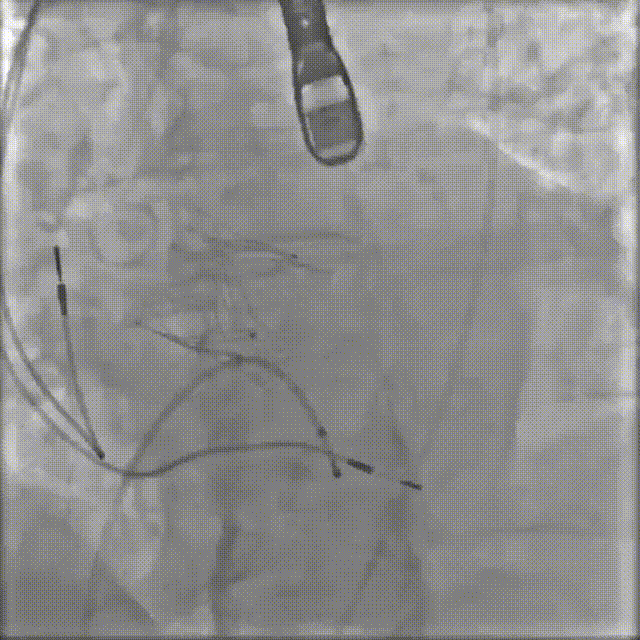

2026年伊始,TaurusTrio经导管主动脉瓣系统在武汉大学人民医院,中国科学技术大学附属第一医院,安徽医科大学第一附属医院,安徽医科大学第一附属医院北区,首都医科大学附属北京安贞医院南充医院,海南省人民医院等多家临床中心成功开展上市后全国首批植入。这不仅是TaurusTrio正式走向广泛临床应用的重要里程碑,更标志着中国单纯主动脉瓣反流介入治疗正式迈入了“心键合璧”的全新纪元。